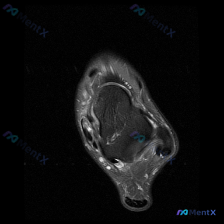

看到一份踝关节T2序列轴位MRI的读片需求,核心问题是「图像中能看到什么软组织积液相关改变」,整理了完整的影像分析和鉴别思路分享给大家。 先整理影像基本信息和发现 这是踝关节远端层面的轴位扫描,主要结构如下: - 骨骼:胫骨远端、腓骨远端、距骨骨髓信号都没有异常,没有片状高信号,排除明确骨髓水肿 -...

踝关节MRI读片分享:双侧腱鞘积液的分析思路 这是一份踝关节MRI T2序列轴位图像的读片病例,整理了影像表现和完整分析思路,和大家一起讨论。 病例影像基本信息 检查:踝关节MRI T2序列轴位,切面位于距骨体水平 影像所见 1. 骨与关节:距骨骨皮质连续性良好,骨髓信号未见异常高信号,关节间隙无明...

今天看到一份踝关节MRI,整理出来和大家分享一下,这个病例很容易只满足于发现「软组织积液」,但其实藏着更关键的问题。 病例影像基本信息 这是踝关节MRI轴位T2序列图像,扫描层面位于踝关节远端,显示胫骨远端及周围软组织结构: - 骨性结构:胫骨远端轮廓完整,未见明显骨质中断,髓腔信号无明显弥漫性骨髓...